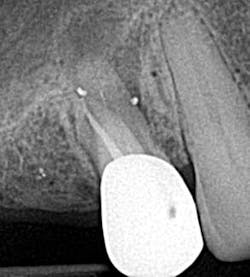

• Underfilling/overfilling

Underfilling of a canal can be caused by blockage, inadequate cleaning and shaping, ledging, and insufficient condensation pressure (figure 4). (1) Prevention is assessment via radiographs with removal and retreatment. Failure of the root canal can ensue, leading to the need for surgery or extraction.